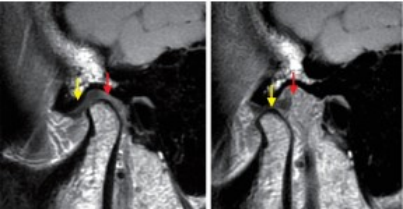

影像学检查:CT检查可观察髁突骨质及结构变化;MRI有助于发现关节盘移位、破裂或穿孔;颞下颌关节镜检查可直接观察关节滑膜的炎症性改变。